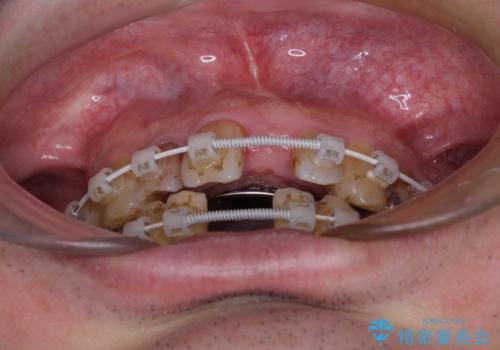

矯正治療を行いながら、欠損部はインプラントによる補綴治療を希望されたため、補助装置を用いたワイヤー矯正によりスペースを確保しながら歯列を整え、適宜インプラントを埋入していくこととしました。

下顎前歯にインプラントを2本埋入するのは非常に困難であり、どうしても歯肉位置に土台の金属色が見えてしまう仕上がりとなりました。無理をせずに1本のみの埋入とするか、ブリッジを提案しましたが、患者様の強い希望により、2本埋入することとなり、大変満足していただけました。